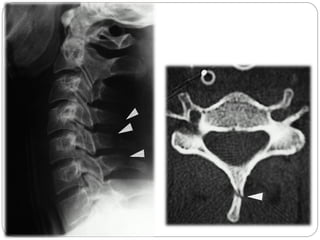

Aspectos Característicos da Cervical

Todas as Vértebras cervicais Possui três forames cada.

C1 ou Atlas Não tem corpo mas tem arco anterior, não tem processo espinhoso, mais massa lateral (pilares articulares).

C2 ou Áxis Possui o Processo odontóide (dente) .

C6 Processos espinhoso curtos com extremidades bífidas.

C7 Chamada vértebra proeminente devido ao seu longo processo espinhoso

1, Corpo Vertebral (T1). 2, Processo Espinhoso C7. 3, Lâmina do arco vertebral. 4, Processo articular inferior. 5, processo articular superior. 6, Processo Espinhoso C2. 7, Processo odontóide (ou dente do áxis). 8, Arco anterior do atlas (C1). 9, Traquéia

SUSPEITAR DE TRAUMA CERVICAL

Toda vítima inconsciente é portadora de TRM até que se prove o contrário;

Qualquer lesão acima da clavícula deve ser investigada para possível lesão de coluna cervical

Aspectos Característicos daCervical Todas as Vértebras cervicais Possui três forames cada. C1 ou Atlas Não tem corpo mas tem arco anterior, não tem processo espinhoso, mais massa lateral (pilares articulares). C2 ou Áxis Possui o Processo odontóide (dente) . C6 Processos espinhoso curtos com extremidades bífidas. C7 Chamada vértebra proeminente devido ao seu longo processo espinhoso

1, Corpo Vertebral(T1). 2, Processo Espinhoso C7. 3, Lâmina do arco vertebral. 4, Processo articular inferior. 5, processo articular superior. 6, Processo Espinhoso C2. 7, Processo odontóide (ou dente do áxis). 8, Arco anterior do atlas (C1). 9, Traquéia

SUSPEITAR DE TRAUMACERVICAL Toda vítima inconsciente é portadora de TRM até que se prove o contrário; Qualquer lesão acima da clavícula deve ser investigada para possível lesão de coluna cervical